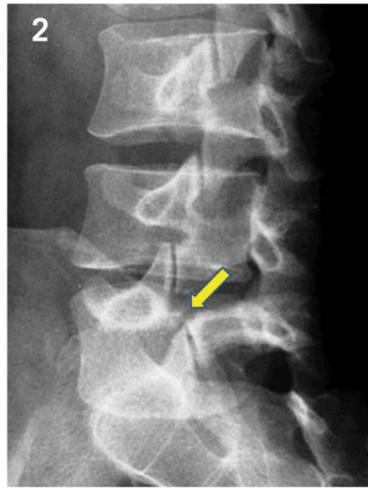

Radiographic “Scottie Dog” Sign

Posterior oblique views show:

- Normal: Scottie dog profile in yellow

- Spondylolysis: Scottie dog appears to be wearing a collar

- Spondylolisthesis: Scottie dog appears decapitated

Diagnostic Imaging

- Lateral view: Shows vertebral slip

- Oblique view: Shows decapitated Scottie dog